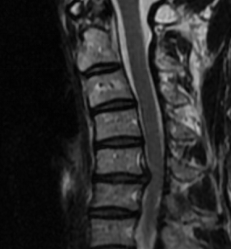

本次接受手术的是一位40岁的年轻患者。因神经根型颈椎病导致持续的颈部疼痛和上肢疼痛麻木,严重影响了日常生活与工作。经我院骨科团队全面评估,认为患者病情符合人工椎间盘置换的适应证:以椎间盘突出等“软性压迫”为主,且颈椎后方小关节退变不明显,活动度良好。

术前颈椎MRI提示颈5/6椎间盘突出明显

面对这样一位对未来生活质量有较高要求的患者,骨科团队没有拘泥于传统方案,而是提出了更具前瞻性的治疗选择。骨科副主任、副主任医师罗肖介绍:“对于符合条件的患者,尤其是年轻、活动需求大的患者,人工椎间盘置换术能让他们在术后依然拥有一个灵活、自然的脖子,这对其长期的生活质量和心理感受至关重要。”